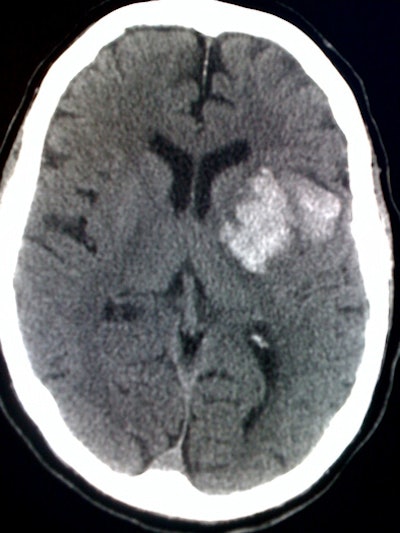

The archived images of the 88 cases in the study were displayed on a digital image monitor, and the iPhone was used to photograph one to three CT images per case. The number of photographs taken depended on the nature of the lesion.

| iPhone digital photo of head CT study. Image courtesy of Marcy Rosenberg, MD. |

Of the 88 cases included in the study, 43 (49%) required no intervention, 29 (33%) required a neurosurgical procedure, seven (8%) required specialized imaging, six (7%) required supportive measures, and three (3%) had nonsurvivable injuries, according to the researchers.